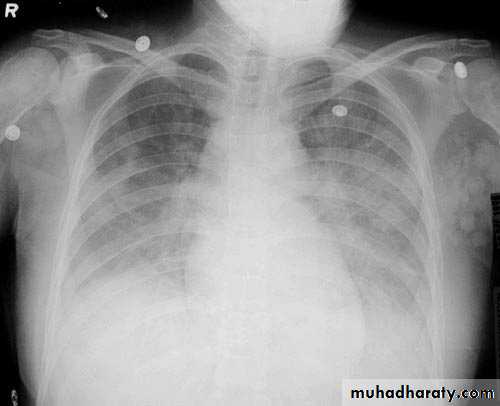

A tension pneumothorax

A tension pneumothorax occurs when intrapleural air accumulates progressively in such a way as to exert positive pressure on mediastinal and intrathoracic structures. It is a life threatening occurrence requiring rapid recognition and treatment is required if cardiorespiratory arrest is to be avoided.Radiographic features

A pneumothorax will have the same features as a run-of-the-mill pneumothorax with a number of additional features, helpful in identifying tension. These additional signs indicate over expansion of the hemithorax:

ipsilateral increased intercostal spaces

shift of the mediastinum to the contralateral side

depression of the hemidiaphragm

tension pneumothorax